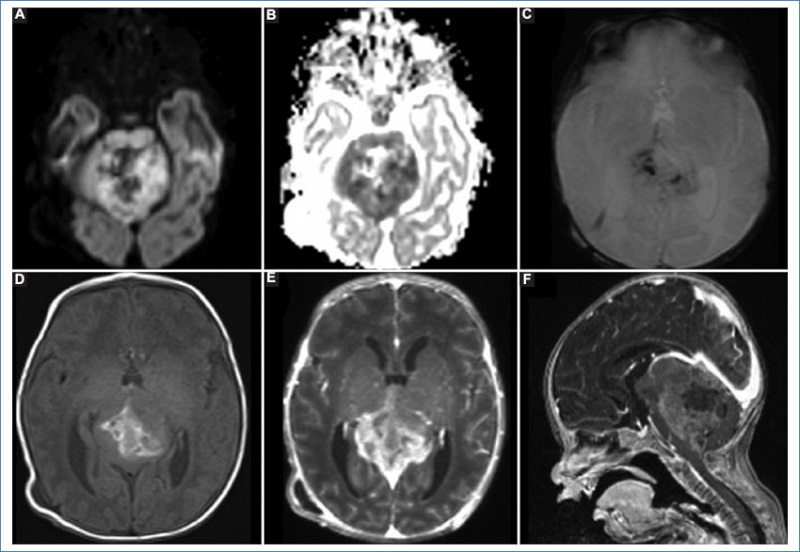

Dentro de los tumores embrionarios, los más frecuentes son el meduloblastoma y el tumor teratoide rabdoide atípico. Ambos tienen un comportamiento similar en la RM dada su alta celularidad, viéndose en la fosa posterior una masa heterogénea debido a la presencia de hemorragia, quistes y calcificaciones. Son iso- o hipointensos en la secuencia ponderada en T1 (con focos de alta señal en caso de hemorragia) e hipointensos en T2, y presentan marcada restricción en difusión. El meduloblastoma tiene una incidencia del 30-40% dentro de los tumores de fosa posterior, con un pico a los 3-4 años y otro a los 7-10 años, lo cual coincide con la ausencia de este tumor en la población estudiada. El tumor teratoide rabdoide atípico de fosa posterior tiene una incidencia menor del 5% en la población pediátrica, pero dentro de los primeros 2 años de vida alcanza un 25%. En un 50% de los casos se ubican en el ángulo pontocerebeloso. Al momento del diagnóstico, un 10-30% de los pacientes presentan diseminación7. El tratamiento suele ser multimodal, con una supervivencia a 5 años del 30% y peor pronóstico en los pacientes menores de 6 meses en el momento del diagnóstico3. En nuestro estudio, dos pacientes de 1 y 6 meses de vida presentaron tumor teratoide rabdoide atípico, encontrándose ambos en la fosa posterior, pero ninguno de ellos en el ángulo pontocerebeloso (APC), sino que se localizaron en el hemisferio cerebeloso izquierdo uno y en la línea media el otro. Presentaban las características imagenológicas descritas en la literatura (Fig. 1) y uno de ellos se asoció a diseminación leptomeníngea. Ambos pacientes recibieron tratamiento quirúrgico; uno murió durante el procedimiento y el otro en el periodo posquirúrgico.